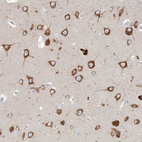

Immunohistochemistry analysis in human testis and liver tissues using HPA036678 antibody. Corresponding FARSB RNA-seq data are presented for the same tissues.